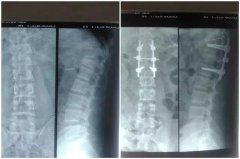

千斤钢棚“砸断腰”,两次手术23天走起!

近日,一名中年男子来到深圳万丰医院,把一面鲜艳的锦旗送给骨科医护人员。虽然他腰上佩戴着支撑身体的护具,走路明显较正常人缓慢,但神情却很轻松,脸上带着笑容。这是怎么回事? ▲...